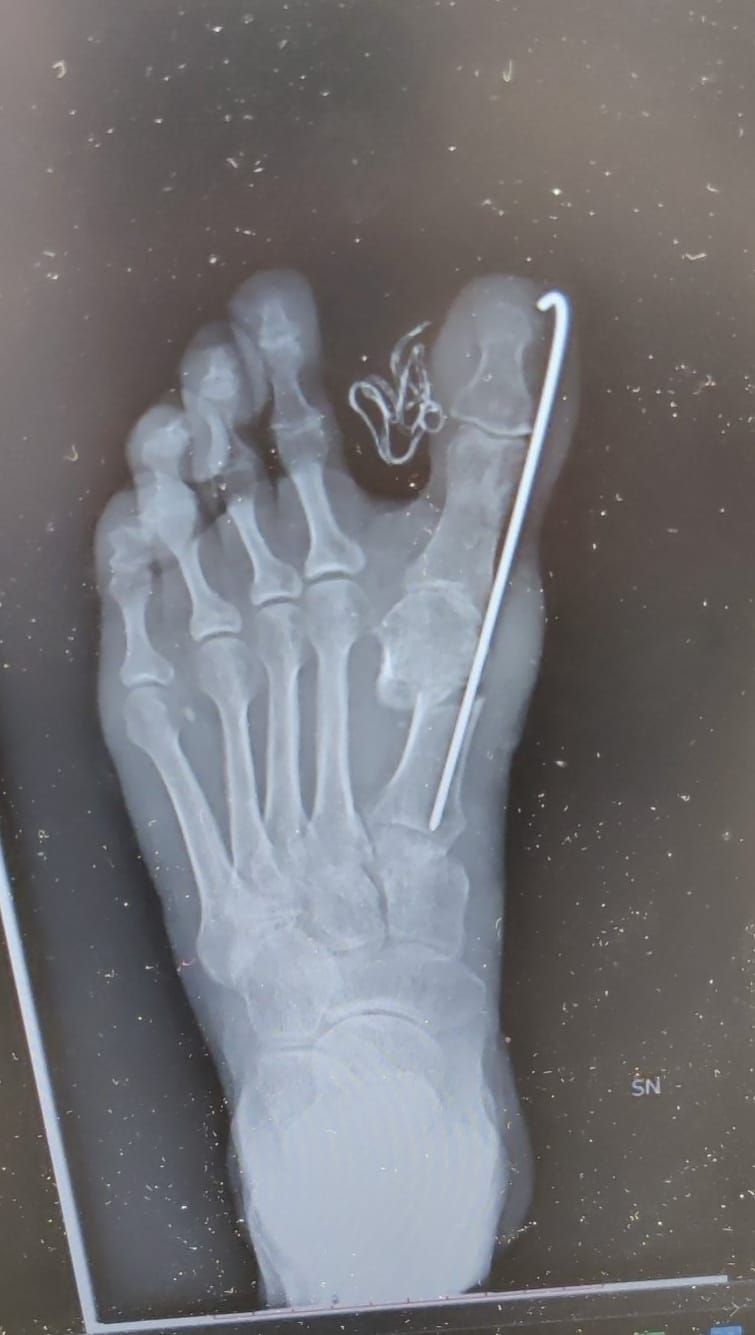

• Ortopedia del piede

• Riduzione chiusa di frattura delle falangi del piede senza fissazione interna

Da 80 €